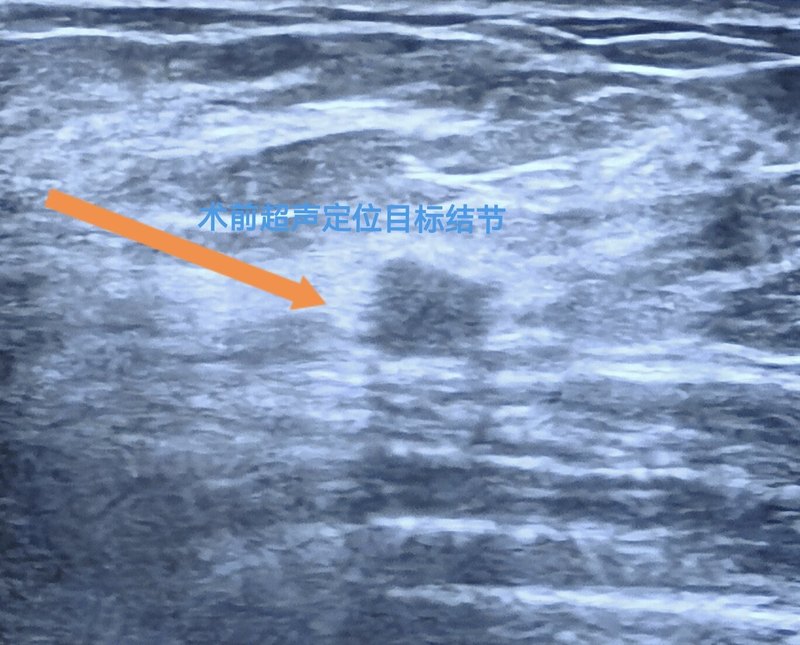

乳腺微創(chuàng)旋切術(shù),也稱為真空輔助乳腺活組織檢查(VAB),是一種在超聲引導(dǎo)下進(jìn)行的微創(chuàng)手術(shù),主要用于性質(zhì)不明結(jié)節(jié)活檢,或切除乳腺結(jié)節(jié)、良性腫瘤。以下是關(guān)于乳腺旋切術(shù)前后的一些重要注意事項(xiàng)。患者:王醫(yī)生,我過(guò)幾天要做乳腺旋切術(shù),心里有點(diǎn)緊張,您能跟我說(shuō)說(shuō)術(shù)前要準(zhǔn)備什么嗎?王醫(yī)生:別擔(dān)心,術(shù)前準(zhǔn)備挺簡(jiǎn)單的。首先我會(huì)與你詳細(xì)聊聊,這個(gè)手術(shù)是否適合你。當(dāng)然,根據(jù)你的情況,是非常適合做這個(gè)手術(shù)的。手術(shù)要避開(kāi)月經(jīng)期,最好在月經(jīng)干凈后到下次月經(jīng)來(lái)臨前5天做。還有,手術(shù)前5-7天內(nèi)不吃抗凝藥,比如阿司匹林、華法林、氯吡格雷,不然手術(shù)時(shí)容易出血?;颊撸号?,好的,那我還需要做哪些檢查呢?王醫(yī)生:你得做血常規(guī)、凝血功能、肝腎功能、心電圖等,還有乳腺超聲定位,這樣我們能評(píng)估你的健康狀況和腫塊的位置?;颊撸好靼琢?,那手術(shù)當(dāng)天有什么要注意的嗎?王醫(yī)生:手術(shù)是日間手術(shù),在醫(yī)院的時(shí)間很短,但當(dāng)天你要空腹,手術(shù)前別吃喝東西。記得穿寬松舒適的衣服,方便穿脫。患者:好的,那手術(shù)過(guò)程是怎樣的呢?王醫(yī)生:手術(shù)時(shí),我們會(huì)用超聲引導(dǎo),通過(guò)一個(gè)5毫米的小切口,用真空輔助活檢系統(tǒng)精準(zhǔn)切除腫塊。這種方法創(chuàng)傷小、恢復(fù)快,你不用太擔(dān)心。另外,術(shù)后要持續(xù)壓迫胸部手術(shù)位置約20分鐘?;颊撸耗切g(shù)后要注意什么呢?王醫(yī)生:術(shù)后要加壓包扎3-5天,以防出血??噹e自行松解,如果太緊影響呼吸或看到血跡,及時(shí)找我。還有,術(shù)后4周內(nèi)別做劇烈運(yùn)動(dòng),不要擴(kuò)胸、游泳、跑步、打球、上肢大幅度甩動(dòng)、手提重物等,避免拉扯到傷口。但要保持肩關(guān)節(jié)適度活動(dòng),以防肩周痛。日常家務(wù)可以量力而行,避免牽扯胸部。患者:如果術(shù)后感到疼痛怎么辦?王醫(yī)生:術(shù)后當(dāng)天輕微疼痛是正常的,過(guò)幾天就好了。如果疼痛劇烈,或者出現(xiàn)高熱、出血不止、淤血腫脹,可能是并發(fā)癥,得趕緊找我。個(gè)別人會(huì)在術(shù)后一個(gè)月開(kāi)始出現(xiàn)活動(dòng)時(shí)疼痛,這是組織修復(fù)過(guò)程中的牽涉痛,不用處理?;颊撸耗莻谝趺醋o(hù)理呢?王醫(yī)生:術(shù)后初期,要保持傷口干燥清潔,別沾水??噹Р鹆撕?,可以貼防水創(chuàng)口貼洗澡,但不能泡澡、搓揉乳房。建議佩戴緊身胸罩支撐乳房,保護(hù)創(chuàng)面?;颊撸何衣?tīng)說(shuō)會(huì)出現(xiàn)術(shù)后血腫,是怎么回事?王醫(yī)生:乳腺結(jié)節(jié)旋切后,原結(jié)節(jié)處會(huì)形成空腔而滲血,因此術(shù)后血腫挺常見(jiàn)的,表現(xiàn)為皮膚青紫。大多數(shù)小血腫會(huì)自行吸收,大的血腫可以穿刺抽吸,不用太擔(dān)心。但如果出現(xiàn)發(fā)熱、紅腫,可能發(fā)生感染了,要及時(shí)找我。患者:那術(shù)后多久要復(fù)查呢?王醫(yī)生:術(shù)后一周就復(fù)查,檢查傷口愈合情況,并解讀病理報(bào)告。根據(jù)病理結(jié)果,我們會(huì)告知你后續(xù)治療計(jì)劃?;颊撸耗俏乙院筮€要復(fù)查呢?王醫(yī)生:因?yàn)槿橄傥?chuàng)手術(shù)只是切除現(xiàn)有的乳房結(jié)節(jié),沒(méi)有預(yù)防結(jié)節(jié)復(fù)發(fā)/再發(fā)的作用,因此術(shù)后半年要復(fù)查彩超,看看是否有其他結(jié)節(jié)變化,尤其是多發(fā)結(jié)節(jié)的人更要按時(shí)復(fù)查。彩超復(fù)查時(shí),原手術(shù)位置可能出現(xiàn)小囊腫或瘢痕性不規(guī)則回聲結(jié)節(jié),是正常術(shù)后改變,不必過(guò)分擔(dān)心?;颊撸何衣?tīng)說(shuō)手術(shù)后,有的人乳房會(huì)凹陷,有的人會(huì)出現(xiàn)更大的硬塊?王醫(yī)生:乳腺旋切術(shù)后,乳房?jī)?nèi)手術(shù)區(qū)會(huì)留下一個(gè)空腔,機(jī)體會(huì)通過(guò)疤痕方式自我修復(fù)。這時(shí)有人會(huì)感覺(jué)到硬塊或查B超發(fā)現(xiàn)邊界不清的低回聲結(jié)節(jié),這些通常在3-6個(gè)月內(nèi)吸收。部分乳腺結(jié)節(jié)位置表淺的患者,術(shù)后可能出現(xiàn)皮膚凹陷,但會(huì)隨時(shí)間恢復(fù),不用太擔(dān)心?;颊撸汉玫模颐靼琢?。那術(shù)后還需要注意什么?王醫(yī)生:我們發(fā)現(xiàn)好多乳腺結(jié)節(jié)患者常伴乳腺腺病,表現(xiàn)為周期性乳房腹痛。因此,建議大家保持樂(lè)觀心態(tài),養(yǎng)成良好生活習(xí)慣,并定期到??茩z查,每個(gè)月做好乳房自我檢查。

超聲引導(dǎo)下的乳腺腫物微創(chuàng)旋切術(shù)是一種高效、安全的微創(chuàng)診斷以及治療技術(shù)。廣泛應(yīng)用于乳腺良性腫物的切除以及部分早期可疑癌變的活檢切除。手術(shù)步驟1.術(shù)前結(jié)合超聲以及鉬靶檢查明確病灶的大小以及位置。醫(yī)生結(jié)合實(shí)際情況設(shè)計(jì)合適的手術(shù)路徑。2.局部麻醉手術(shù)中僅在病灶部位注射局麻藥物,患者全程無(wú)明顯疼痛感。3.旋切腫物操作精準(zhǔn)引導(dǎo):在超聲實(shí)時(shí)引導(dǎo)下,術(shù)者將旋切針頭插入病灶區(qū)域。通過(guò)釋放刀槽確認(rèn)腫物契合在刀槽內(nèi)。4.可視化旋切:通過(guò)針頭的高速旋轉(zhuǎn),完整切除病灶,同時(shí)利用負(fù)壓吸引系統(tǒng)迅速移出體外。全程在超聲影像監(jiān)測(cè)下操作,確保切除范圍精準(zhǔn)、操作安全。5.術(shù)后切口無(wú)需縫合,僅需粘合。術(shù)后切口隱蔽,恢復(fù)快,對(duì)乳房外觀無(wú)明顯影響?;颊哧P(guān)注的問(wèn)題1.是否會(huì)影響乳腺功能?微創(chuàng)旋切僅切除病變組織,對(duì)乳腺結(jié)構(gòu)和功能影響很小,術(shù)后對(duì)哺乳功能不能說(shuō)絕對(duì)不影響,但概率極低。2.術(shù)后復(fù)發(fā)可能性?對(duì)于良性腫物,徹底切除后復(fù)發(fā)概率很低。但需定期復(fù)查排除其他新發(fā)病變。以上為微創(chuàng)手術(shù)的流程簡(jiǎn)介。對(duì)于乳腺良性可能大結(jié)節(jié),優(yōu)選觀察,次選微創(chuàng),再次選開(kāi)刀手術(shù)。